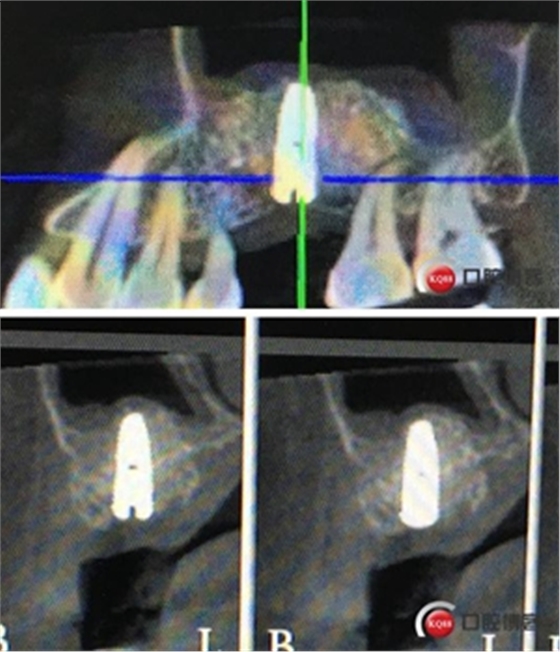

植入一顆4.5x11.5mm長度植體。

植入后X光片。

半年后修復。